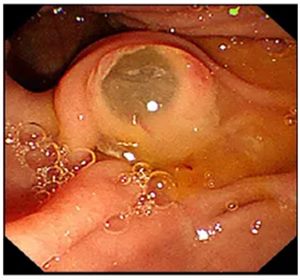

十二指肠主乳头呈现典型的“鱼眼征”,大量透明浓稠粘液不断涌出!导丝顺利插入胰管造影,显示胰管全段扩张。随后置入纤细的胰管镜,内镜下清晰可见胰管内壁布满了白色珊瑚状增生组织——成功获取关键病理!

▲ (胰管内增生组织)考虑为导管内乳头状粘液肿瘤伴低级别异型增生